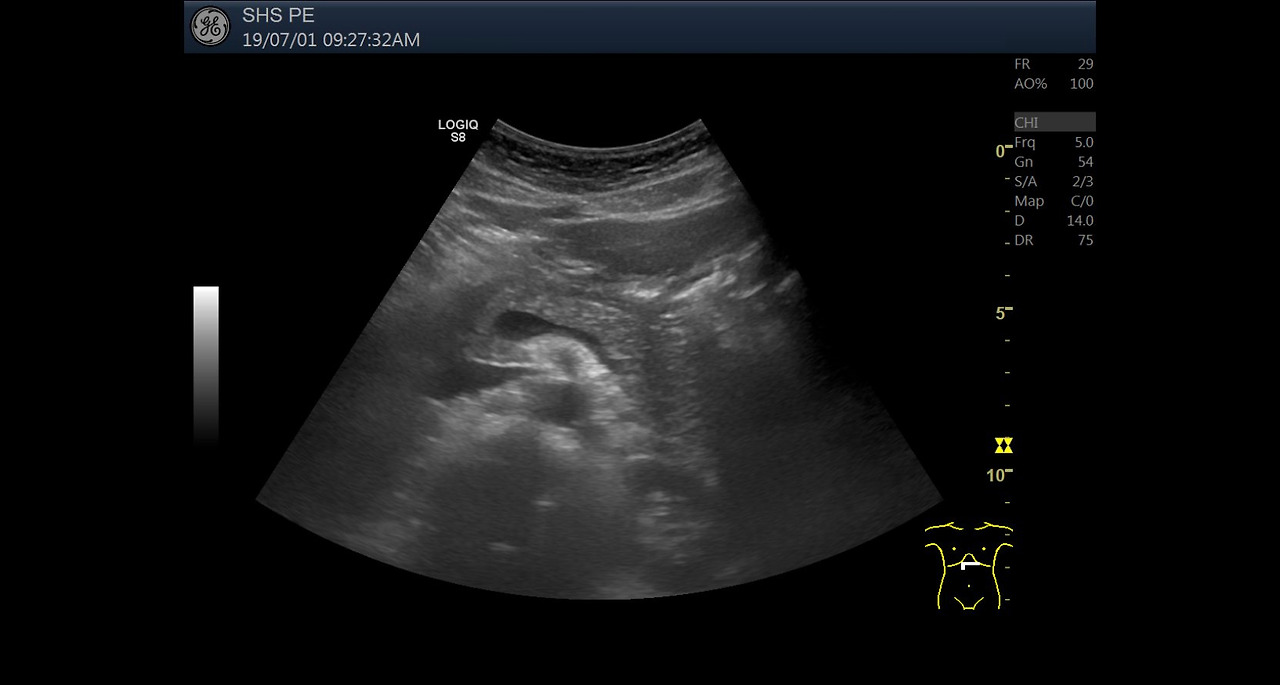

복부 초음파는 비침습적이며 방사선 노출이 없는 안전한 검사 방법으로, 초음파(ultrasound)를 통해 복부 내 장기들의 상태를 실시간으로 확인할 수 있는 진단 도구입니다. 복부 초음파로 알 수 있는 것 중에서는 특히 간, 담낭, 췌장, 비장, 신장, 방광, 대동맥, 소장, 대장 등의 상태를 파악할 수 있으며, 질환의 조기 발견에 탁월한 효과를 보입니다.

- 지방간: 간 조직 내 지방 축적 상태 확인 가능

- 간경화: 간 표면의 거칠음, 크기 변화, 비장 비대 여부 등 확인

- 간암, 간종양: 실질 내부에 덩어리 유무 탐색

- 공기나 뼈로 가려진 장기(예: 위, 장 등)는 시야 확보 어려움

- 지나치게 비만하거나 복부 지방이 많은 경우 해상도 저하